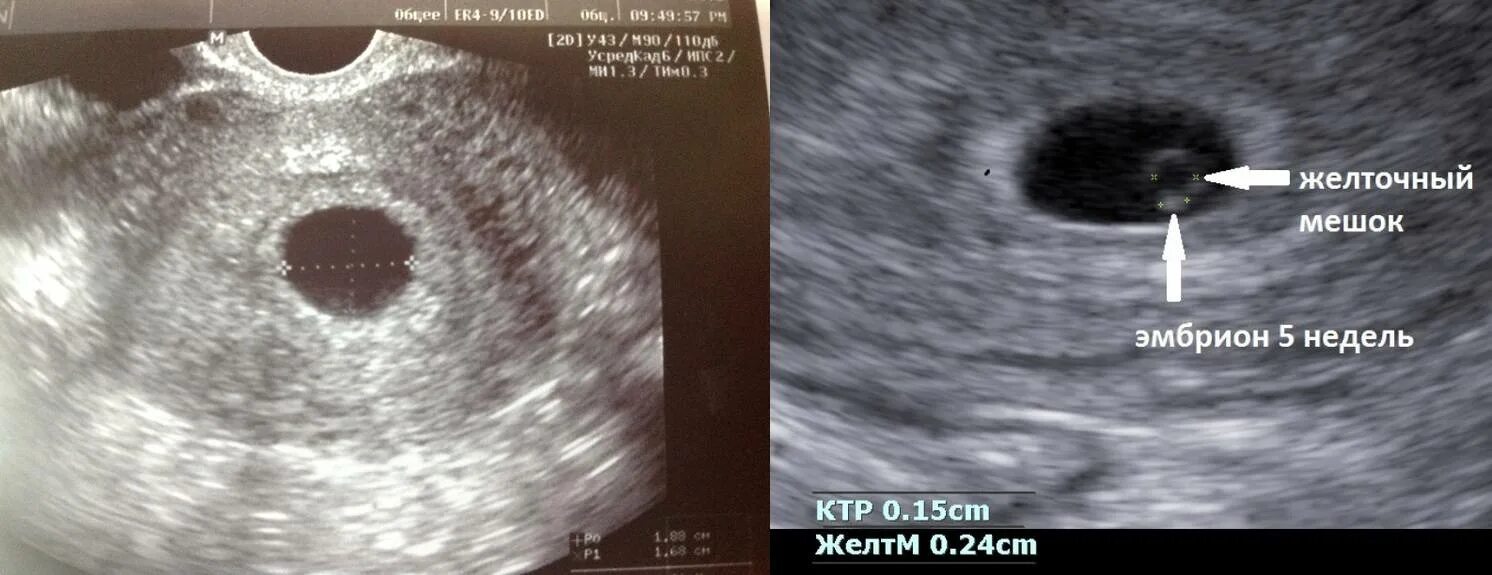

Морозит при беременности на ранних сроках